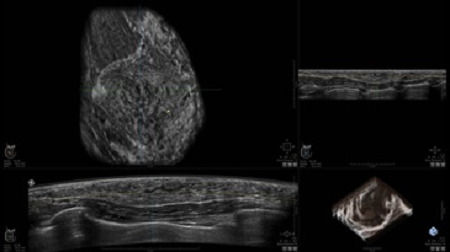

GE INVENIA ABUS – это современный УЗИ аппарат, который создан для точной и эффективной диагностики сканирования с высокой плотностью молочных желез. Выявляемость патологий раковых и предраковых стадий заболевания составляет 55%, что в конечном счете позволяет ставить врачу точные и своевременные диагнозы. Традиционные методы использования маммографии не показывают такой выявляемости, ограничиваясь лишь 3-38%.

УЗИ-аппарат GE INVENIA ABUS позволяет проводить максимально операторонезависимые процедуры, что значительно снижает риск неправильной постановки диагноза и сопутствующие издержки на обработку информации. Система готовит отчет в течение 3-х минут после сканирования, это безусловное преимущество по сравнению с обычным УЗИ сканером.

Данное устройство классифицируется, как стационарное, используемое в многопрофильных клиниках, женских консультациях, медицинских центрах. Вес без учета дополнительного оборудования составляет 105 кг. Удобная колесная база позволяет оперативно маневрировать в ограниченных пространствах, в том числе передвигать устройство в коридорах клиники. Большой 17-ти дюймовый монитор с широкими углами обзора выводит максимально качественную картинку в формате Full HD.

• Получение объемных 3D изображений с возможностью покадрового просмотра

• Отображение объемных 3D ультразвуковых изображений, которые состоят из традиционных поперечных и воссозданных коронарных и сагиттальных проекций

• Возможность отображения полного 3D изображения

• Стандартизованная ориентация изображения: «толстый срез» в коронарной плоскости; поперечная; сагиттальная плоскость; радиальный и антирадиальный поворот изображения; просмотр исключительно области интереса